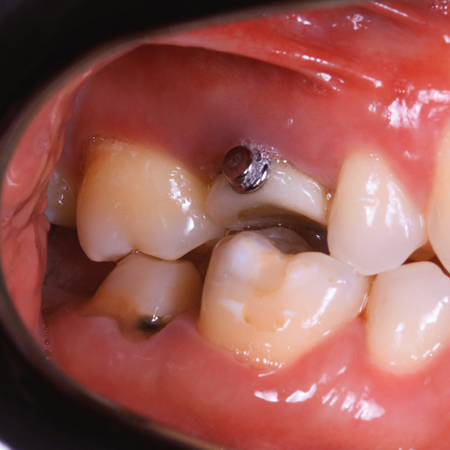

Intrusão do segundo molar superior com ancoragem esquelética

INTRODUÇÃO: A ancoragem esquelética permite intervenções pontuais direcionadas a uma correção prévia à reabilitação protética, seja coroa ou implante dentário. Pacientes com pouca estrutura óssea ou que não permitem tratamento ortodôntico prévio podem apresentar limitações no uso da ancoragem esquelética. OBJETIVO: Apresentar um relato de caso clínico envolvendo a intrusão de um segundo molar superior para correção do espaço interoclusal, possibilitando a reabilitação de seu antagonista. Trata-se de um caso com resolução rápida e eficaz, no qual a instalação...

INTRODUÇÃO: A ancoragem esquelética permite intervenções pontuais direcionadas a uma correção prévia à reabilitação protética, seja coroa ou implante dentário. Pacientes com pouca estrutura óssea ou que não permitem tratamento ortodôntico prévio podem apresentar limitações no uso da ancoragem esquelética. OBJETIVO: Apresentar um relato de caso clínico envolvendo a intrusão de um segundo molar superior para correção do espaço interoclusal, possibilitando a...

Maxillary second molar intrusion with  skeletal anchorage

INTRODUCTION: Skeletal anchorage enables targeted interventions for pre-prosthetic corrections, whether for dental crowns or implants. Patients with limited bone structure or contraindications for prior orthodontic treatment may present limitations in using skeletal anchorage. OBJECTIVE: To present a clinical case report involving the intrusion of an upper second molar to correct the interocclusal space, enabling the rehabilitation of its antagonist. This is a case with a quick and effective...